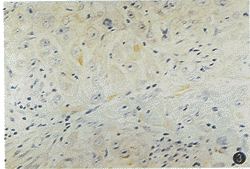

图3 低分化鳞癌免疫组化染色1例,nm23-H1蛋白低染(SABC法×400)

4.nm23-H1蛋白表达水平与口腔鳞癌临床病理指标的关系:χ2检验发现,nm23-H1蛋白表达水平同肿瘤的大小、部位、患者的年龄、性别及临床分期无明显关系;与口腔鳞癌的颈淋巴结转移及病理分级有关。淋巴结转移组高染率为15.15%(5/33),无淋巴结转移组的高染率为52.38%(22/42),两组间差异有极显著性(P<0.01)。在高、中、低分化鳞癌中的高染率分别为48.89%(22/45)、20.00%(4/20)、10.00%(1/10),高分化同中、低分化鳞癌间差异有显著性(P<0.05),见图2、3。